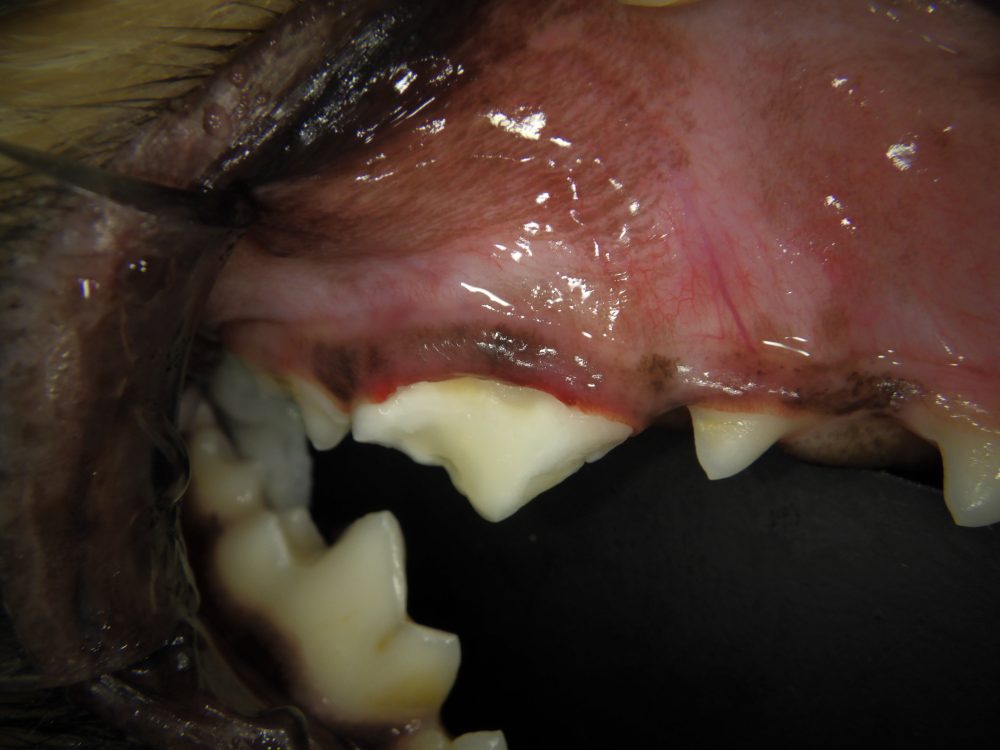

とりあえず顔の腫れや排膿はなく、外観も問題ありませんでした。

歯茎の状態も以下の通り本来の位置に近い位置までクリーピング(伸びてきている)していて歯周病のリスクも低い状態であるのを確認しました。